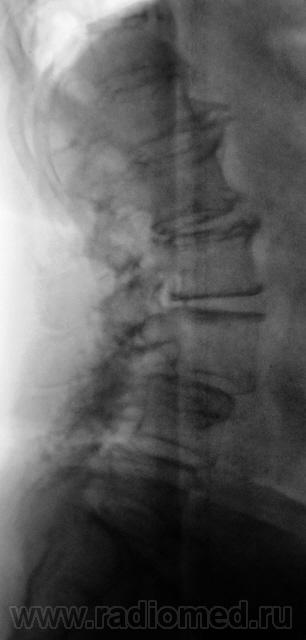

Остеохондроз, деформирующий спондилез поясничного отдела.Антелистез 3 позвонка до 1/4 ( 1 степень). Почему снимки не увеличиваются?

остеохондроз поясничного отдела. Листез 3 позвонка. SPINA bifida posterior